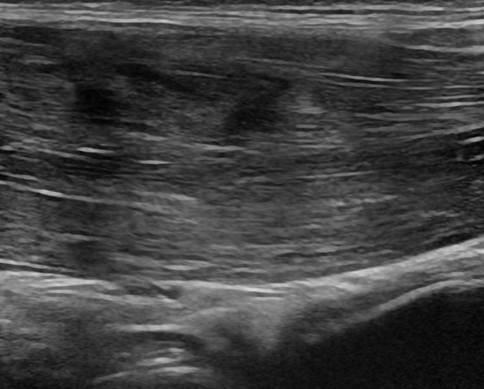

Chấn thương thành bụng

» Thông tin: Nam giới – 18 tuổi.

» Lâm sàng: Chấn thương thành bụng.

# Đụng dập, tụ máu cơ thành bụng.